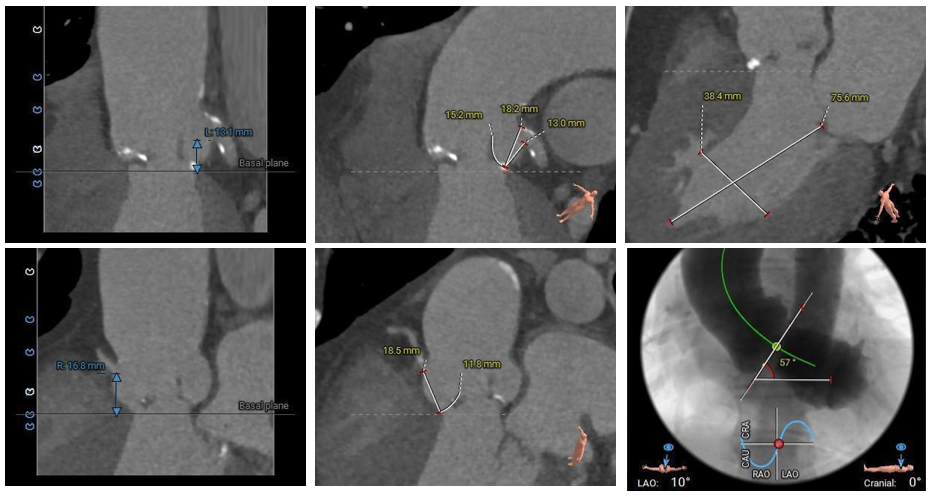

术前CT评估:

•Type 1 型二叶式主动脉瓣,R-N间钙化融合嵴,瓣叶增厚伴轻中度钙化,左窦内钙化延伸至瓣环平面;左室流出道呈敞口型。

•冠脉开口高度可,左冠瓣叶冗长,左冠切线位瓣叶长度>冠脉开口到瓣叶附着缘距离;冠脉可见散在钙化斑块。

•瓦氏窦、窦管交界内径尚可,升主动脉扩张;左室腔内径正常,心室壁厚度尚可。

•瓣环水平夹角为57°,主动脉弓弓距、角度可,升主动脉未见明显扭曲。

•双侧股髂动脉未见扭曲,主动脉弓、降主动脉、腹主动脉、右髂总动脉可见多发散在钙化斑块,股动脉穿刺处未见明显钙化,右股动脉分叉处较高,入路血管直径尚可。

主动脉根部测量

瓣上结构测量

冠脉阻挡风险及左室大小评估

外周血管入路评估